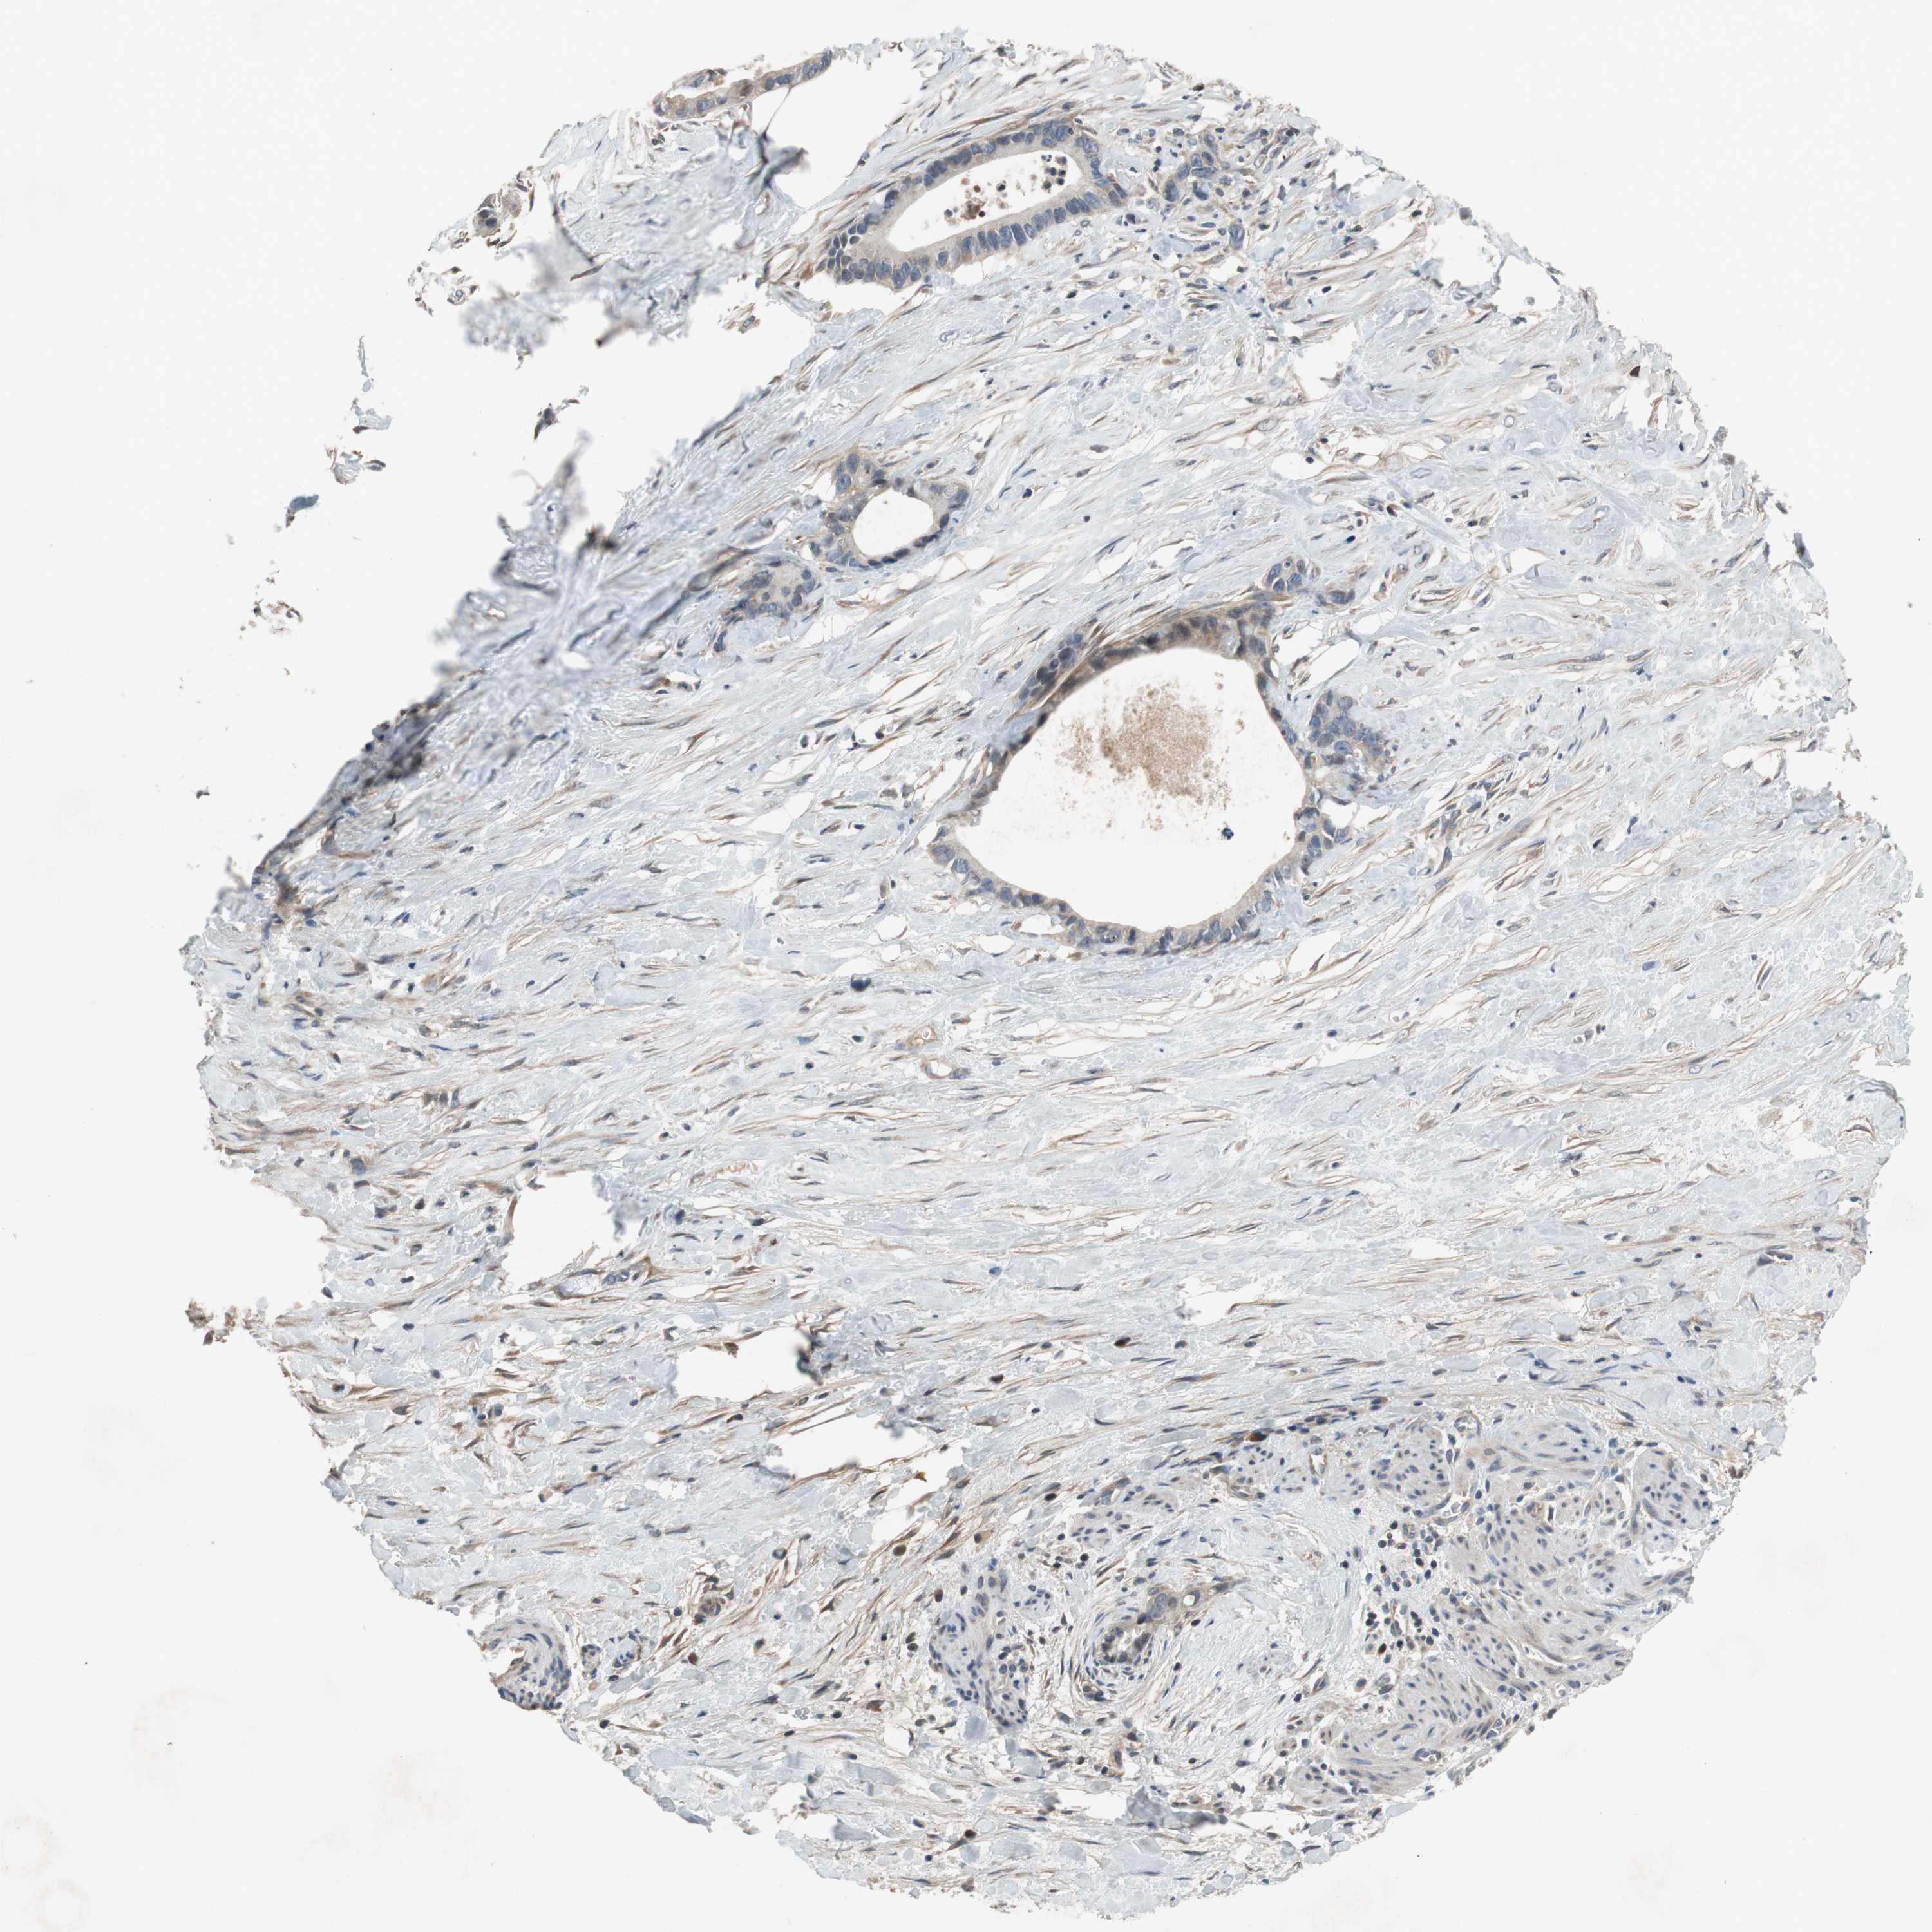

LIVER CANCER - Protein expressioni

A mouse-over function shows sample information and annotation data. Click on an image to view it in a full screen mode. Samples can be filtered based on level of antibody staining by selecting one or several of the following categories: high, medium, low and not detected. The assay and annotation is described here.

Note that samples used for immunohistochemistry by the Human Protein Atlas do not correspond to samples in the TCGA dataset.

Antibody stainingi

Antibody staining in the annotated cell types in the current human tissue is reported as not detected, low, medium, or high, based on conventional immunohistochemistry profiling in selected tissues. This score is based on the combination of the staining intensity and fraction of stained cells.

Each image is clickable and will lead to virtual microscopy that enables deeper exploration of all samples and also displays staining intensity scores, fraction scores and subcellular localization as well as patient and tissue information for each sample.

HPA046356

HPA048287

HPA050103

CAB009811

CAB032603

Cholangiocarcinoma

Carcinoma, Hepatocellular, NOS